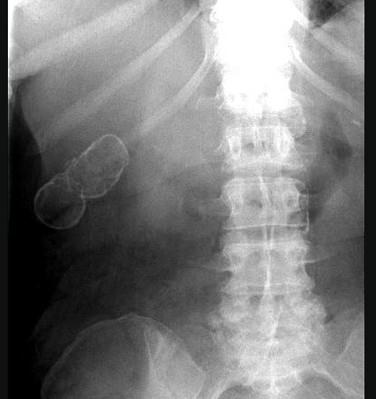

问题 女,39岁,右上腹部隐痛,有慢性胆囊炎史,曾经做过口服胆囊造影,胆囊未正常显影,X线检查如图,最可能的诊断是 ( )

选项 A、瓷样胆囊 B、胆囊结核 C、慢性胆囊炎 D、胆囊结石 E、急性胆囊炎

答案 A